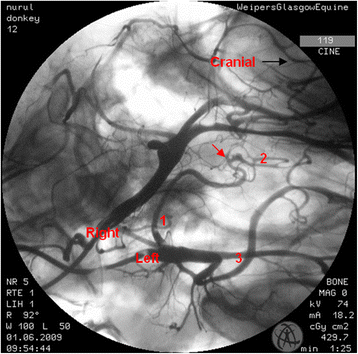

In the region of the intracranial portion of the internal carotid artery, the presence of the caroticobasilar arteries could be appreciated in 20 donkeys, either unilaterally (10) or bilaterally (10). Figure 6 shows an example of the unilateral presence of this artery and Fig. 7 a bilateral example. However, several eccentric connections were seen in addition to this artery in a number of donkeys (3/26). In two donkeys, a small vessel originating from the second curve of the sigmoid flexure of the left internal carotid artery was noted to be connected to the caudal intercarotid artery (Fig. 8). In another donkey, an eccentric connection was seen on the left side where a vessel originating from the second curve of the sigmoid flexure was observed to join the caudal communicating artery before that artery joined the basilar artery to form the caudolateral quadrants of the cerebral arterial circle (Fig. 9). Unfortunately, it was difficult to determine whether this was a true vessel or superimposition with other vessel. In one donkey, it was thought that the caudal intercarotid artery was absent; however its presence was confirmed with repeated views using the Cine-Loop function.

Dorsoventral angiogram of the common pattern of the internal carotid arteries and formation of the cerebral arterial circle of a donkey. Note the bilateral presence of caroticobasilar arteries (red arrows). 1 internal carotid artery; 2 intercarotid artery; 3 caudal communicating artery; 4 basilar artery